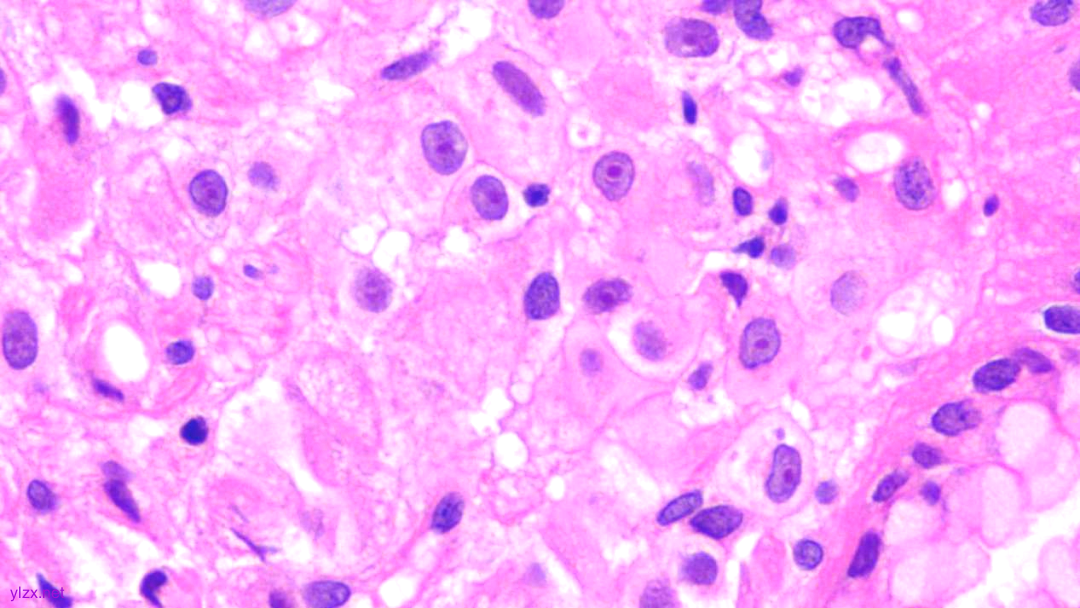

瘤细胞核圆形,见核仁,部分细胞核偏位,未见核分裂象

瘤细胞核仁明显